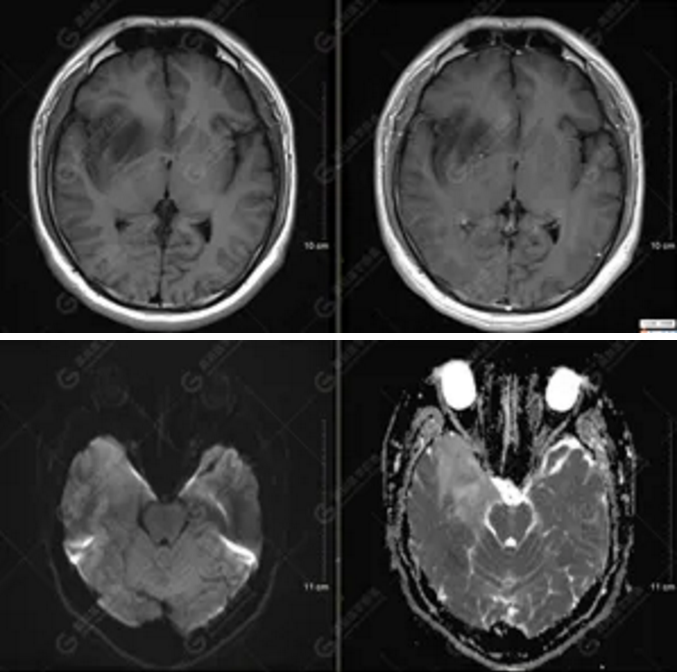

【MRI平掃及增強(qiáng)檢查所見(jiàn)】右側(cè)額顳島葉、右側(cè)海馬及右側(cè)基底節(jié)區(qū)見(jiàn)一團(tuán)塊狀異常信號(hào)影,累及右側(cè)下丘腦及視交叉,大小約5.1cm×4.5cm×4.3cm,呈長(zhǎng)T1長(zhǎng)T2信號(hào),F(xiàn)LAIR序列呈等、稍高信號(hào),DWI序列呈稍高信號(hào),ADC圖高信號(hào),增強(qiáng)后無(wú)明顯強(qiáng)化;病灶周?chē)?jiàn)片狀長(zhǎng)T1長(zhǎng)T2水腫信號(hào)影,F(xiàn)LAIR序列呈高信號(hào),病灶內(nèi)見(jiàn)右側(cè)大腦中動(dòng)脈穿行。余腦實(shí)質(zhì)內(nèi)未見(jiàn)局灶性信號(hào)異常,增強(qiáng)后未見(jiàn)異常強(qiáng)化。右側(cè)側(cè)腦室輕度受壓,余腦室、腦池大小、形態(tài)均正常,中線(xiàn)結(jié)構(gòu)居中

1.右側(cè)額顳島葉、右側(cè)海馬及右側(cè)基底節(jié)區(qū)占位病變,考慮為彌漫性星形細(xì)胞瘤可能性大,累及右側(cè)大腦中動(dòng)脈、右側(cè)下丘腦及視交叉;

彌漫性星形細(xì)胞瘤(WHO Ⅱ級(jí))。